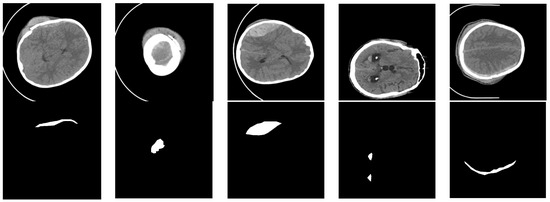

3.1. Image Preprocessing